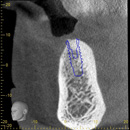

黄色と赤の線で囲まれた所に、サイナスリフトによって骨補てん材が注入されています。

サイナスリフト実施7ヶ月後、インプラント埋入を行いました。